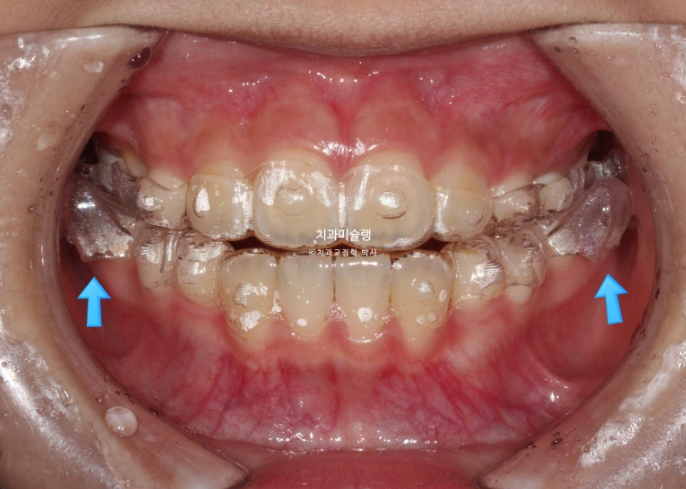

24.02

파란 화살표의 튀어나온 부분을 wing 이라고 부릅니다.

날개같이 생겼기 때문입니다.

위, 아래 장치에 총 4개의 Wing이 불어 나오며 이 Wing 때문에 아래턱을 내밀어 무는 위치로 유도가 됩니다.

근기능장치의 원리는 쉽게 말해 정상 위치에 턱이 적응하게 함으로써 실제로 아래턱뼈가 자라게 해주는 것 이라고 할 수 있겠습니다.